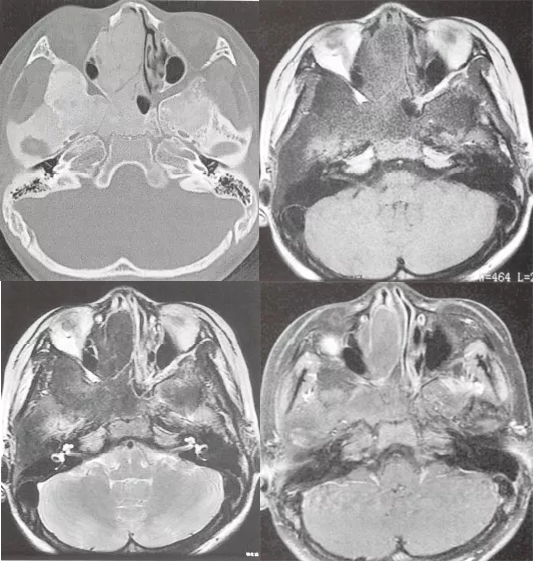

注:颅底骨(颞骨鳞部、右侧蝶骨体、蝶骨大翼、右侧筛窦壁)膨大,呈磨玻璃样改变,右侧翼管、圆孔变窄。T1WI 呈低信号,T2WI 呈低信号,增强 T1WI 呈轻度不均匀强化。

病灶内信号变化与病灶内成分相关,T1WI: 通常为等信号,也可为低信号或混杂信号;T2WI: 通常较低,但可能有信号较高的区域或混杂信号区域;T1WI+C(Gd): 呈不均匀增强。

(注:双侧顶骨板障不均匀增厚,T1WI 呈等、低信号,T2WI 呈稍低信号,增强 T1WI 呈轻度不均匀强化。)